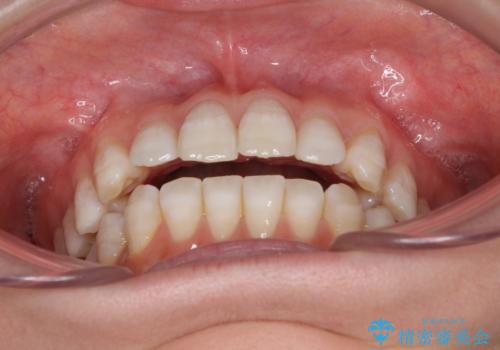

話しにくいオープンバイト インビザラインによる矯正治療

- 前歯の上下スペースによる話しにくさを気にして来院された患者様です。

インビザラインにより上下の前歯の隙間を閉じていくこととしました。

上下の奥歯を圧下させるようにすることで、前歯を接触させるように計画しました。

隙間に舌が入り込むことが話しにくさに繋がっていたため、舌の筋肉のトレーニングも並行して行い、話しにくさの改善と後戻りの抑制を図りました。